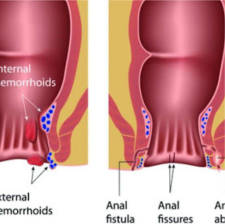

Piles

Hemorrhoids (HEM-uh-roids), also called piles, are swollen veins in the anus and lower rectum. Hemorrhoids are similar to varicose veins. Hemorrhoids can develop inside the rectum, called internal hemorrhoids. They also can develop under the skin ar

Fissures

Fissures result from the stretching of your anal mucosa beyond its normal capacity. This often happens when stools are hard due to constipation. Once the tear happens, it leads to repeated injury. The exposed internal sphincter muscle beneath the tear goes

Fistulas

A fistula is an abnormal connection between two body parts, such as an organ or blood vessel and another structure. Fistulas are usually the result of an injury or surgery.Fistulas can occur throughout your body, either between different organs or from